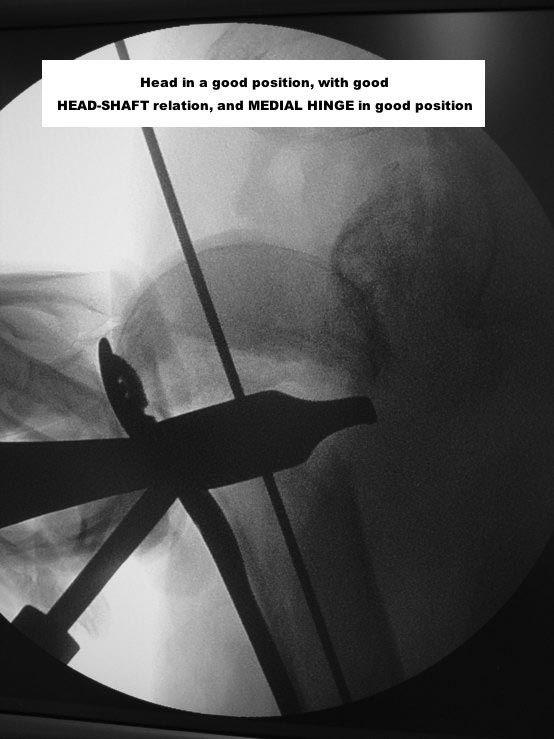

With a good PHILOS, surgeon must re-establish the best cephalic-diaphyseal angle (head-shaft relation) he can, and fix that

Here are some photos, of chronic, locked, 4 part posterior dislocation, 2 months old, that I did September/2011. Patient is 67, very, very active - had a really reasonable, honest clinical result ...

Photos attached ...